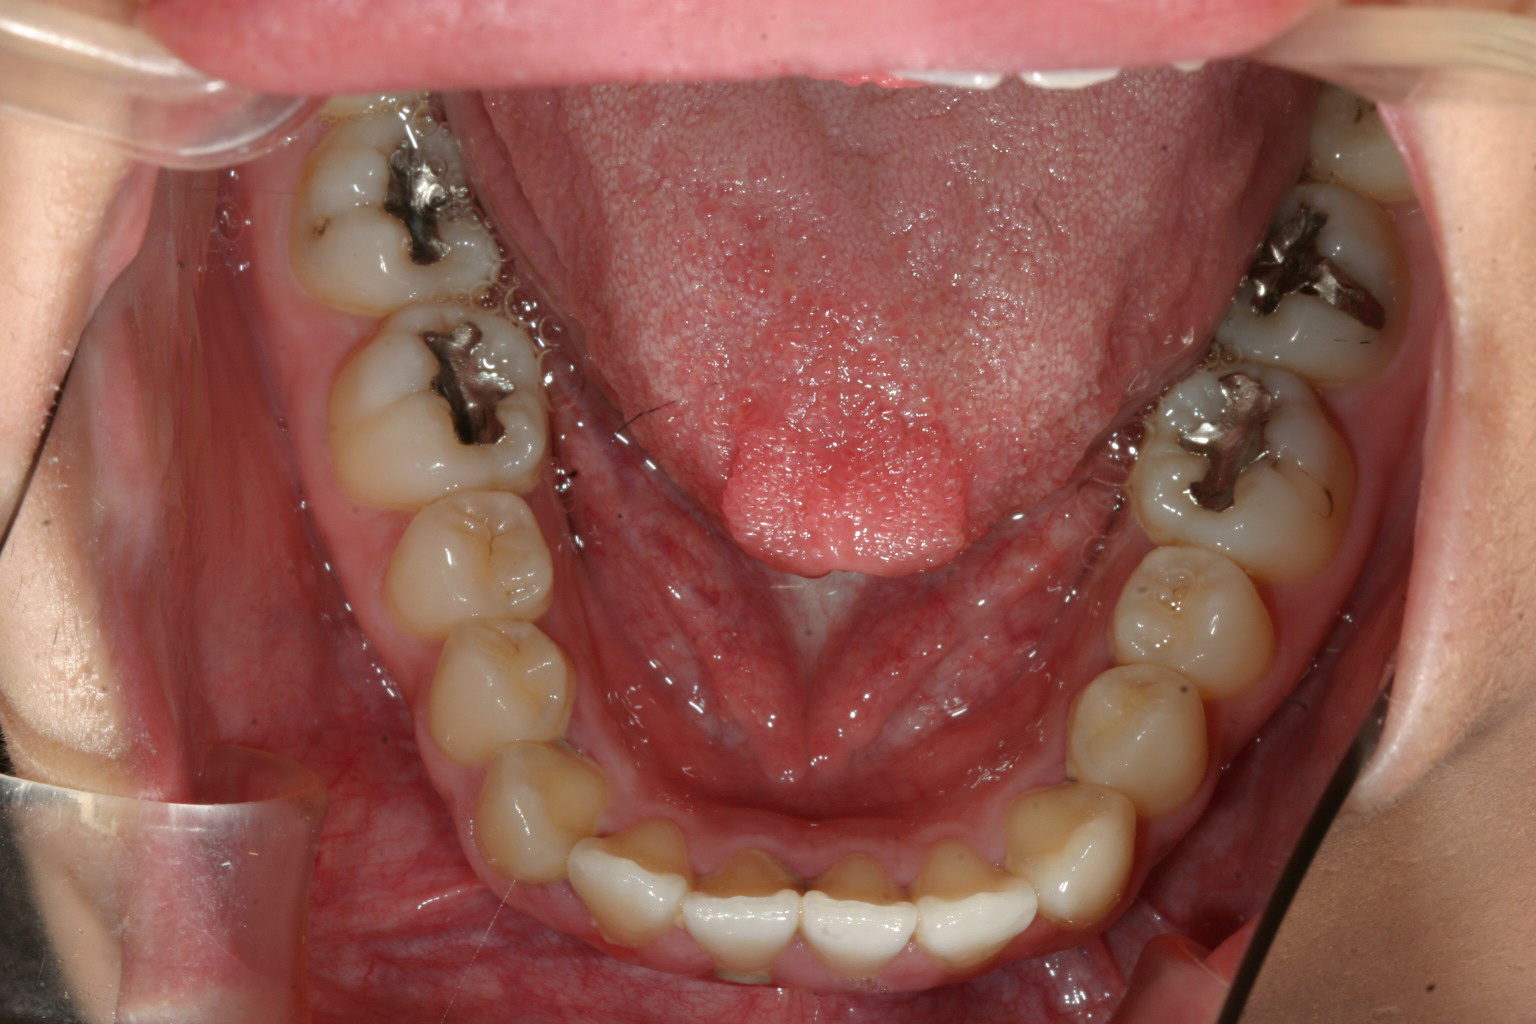

下顎はさほど問題無いですね~

下顎も少し犬歯間を広げてます。